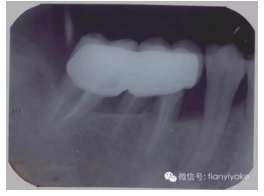

2010年8月 術(shù)后10年零7個月 牙槽骨高度明顯增高,牙齒無松動。左下七舌尖劈裂。2011年3月左下七根管治療,11月行左下六、七烤瓷聯(lián)冠修復(fù)。

p.png

2014年9月左下六七復(fù)查片。